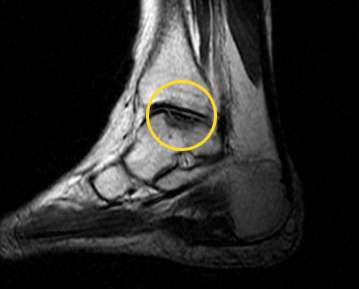

MRT-Untersuchung des Sprunggelenks

Wichtige MRT-Befunde bei Osteochondrosis dissecans:

- Beurteilung des unter dem Knorpel liegenden (subchondral) Knochens

- Ödeme als Hinweis auf eine Nekrose

- Verschmälerung des Gelenkknorpels

- freie Knochenfragmente

Die kernspintomographische Untersuchung (MRT) ist bei der Diagnostik einer Osteochondrosis dissecans am zuverlässigsten. Die MRT ermöglicht dem Arzt auch die Stadieneinteilung der Erkrankung.

Die MRT zeigt die genaue Größe des Dissekats (Gelenkmaus), die Abgrenzung zum umgebenden Knochen, eine Sklerosierung und die Situation im Gelenkknorpel. Im Frühstadium der OD kann das MRT die für eine Knochennekrose typischen Wassereinlagerungen (Ödeme) im Talus zeigen.